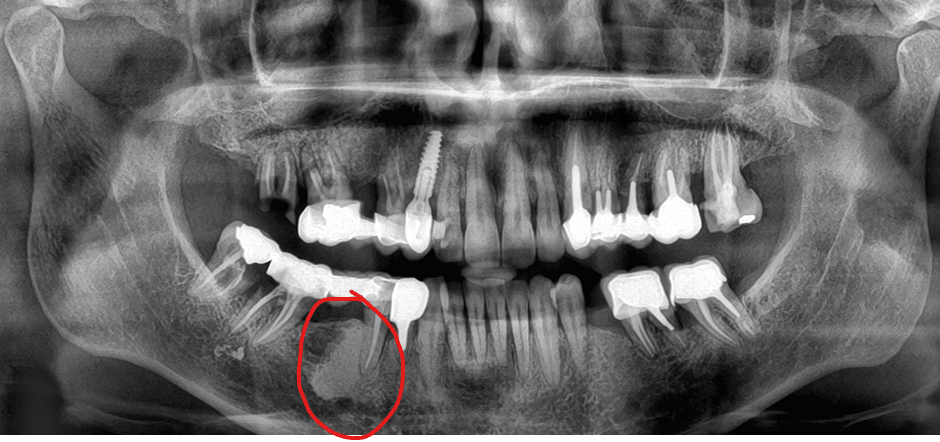

A votre avis c'est quoi ?

c'est un cementome

Ca y ressemble bien en effet. Pas de symptômes, pas toucher. Vérifier au prochain contrôle.

c'est pas son plus gros problème